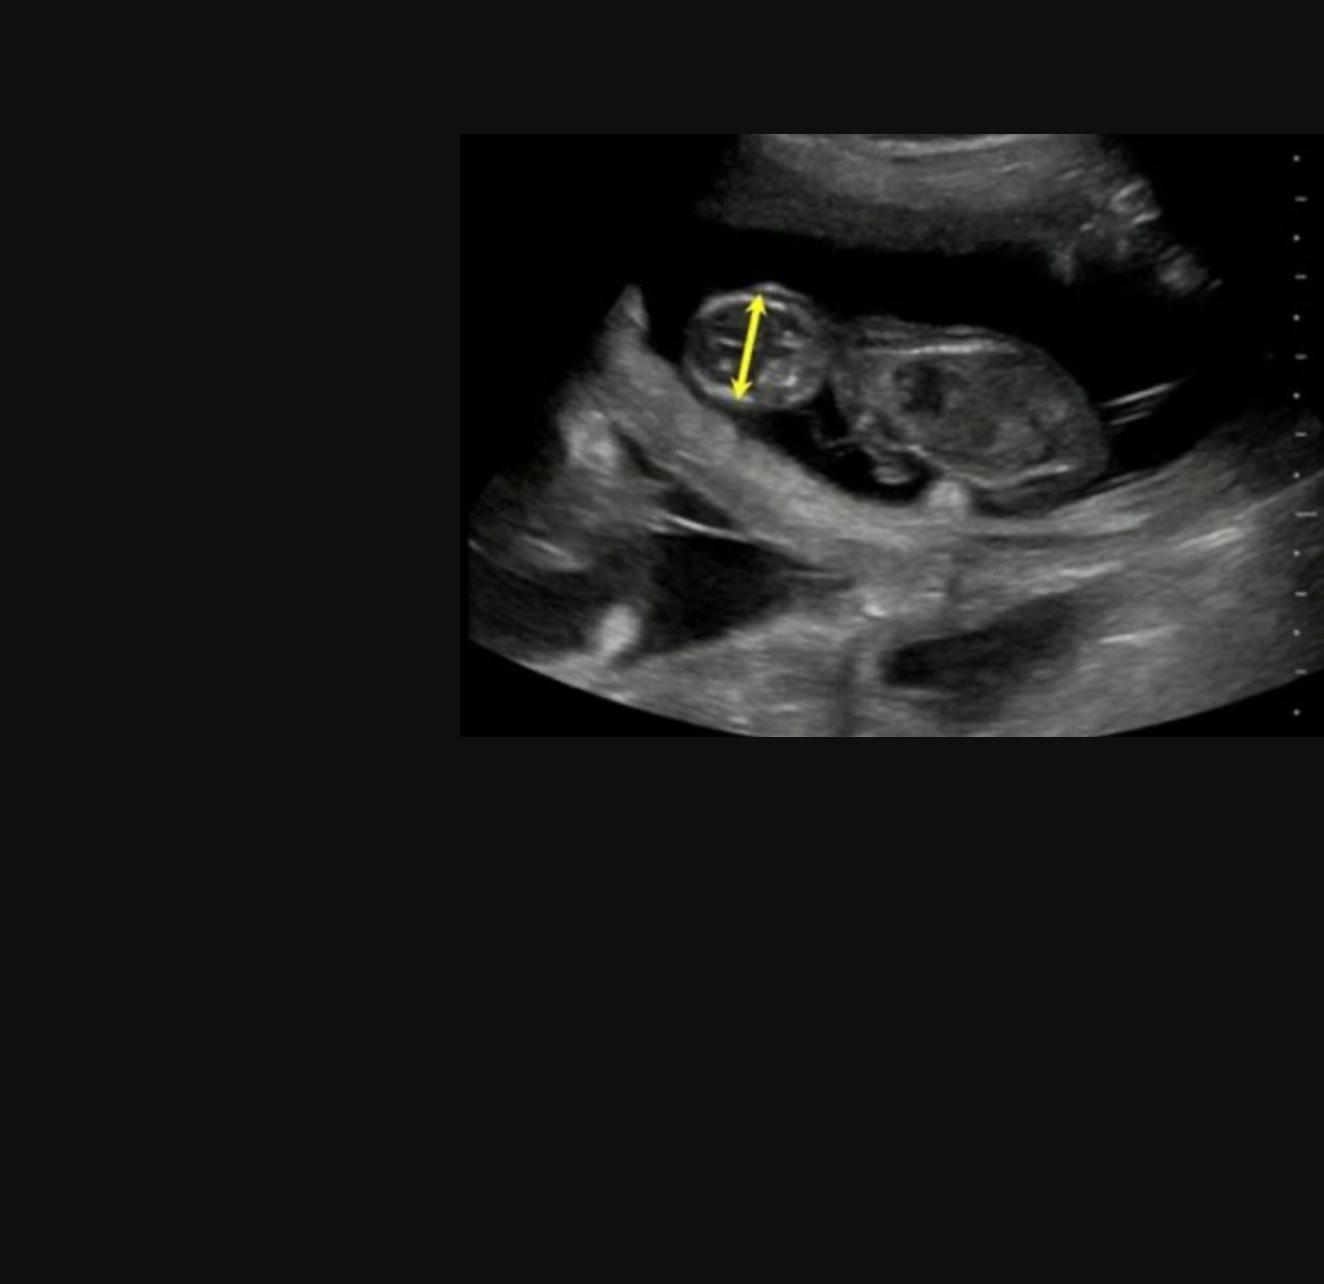

We are also licenced and certified in Canine Fertility. Our services include ultrasound, Artificial Insemination, Semen Analysis, Microchipping and Cytology.

We are the experts when it comes to Canine Fertility. Male & Female Anatomy, Semen Analysis, Cytology Analysis, Ultrasounds and Microchipping.